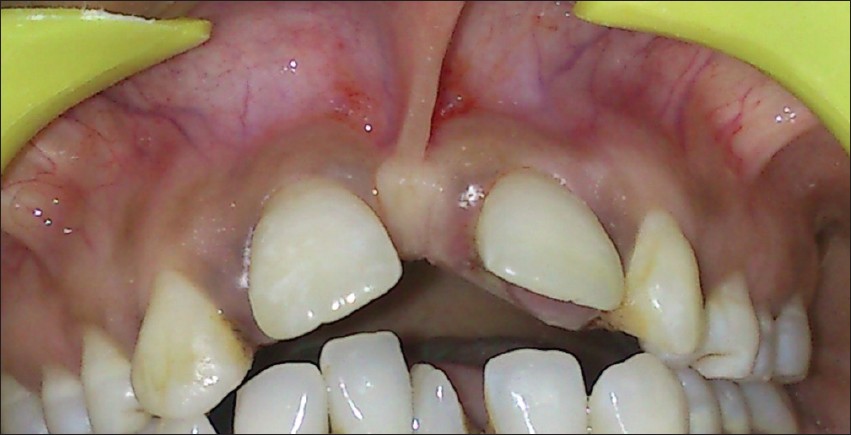

Combined treatment of a lateral incisor with palato-radicular groove: 1 year follow-up |

p. 163 |

Gülen Kamak, Sümeyra Akman DOI:10.4103/2278-9626.134852 Periodontic - endodontic lesion with a palato-radicular groove as a contributing factor for periodontitis is the most important diagnostic and therapeutic challenges faced by periodontists and the maxillary lateral incisors are the most frequently affected teeth. These developmental grooves promotes the accumulation of plaque and calculus, which destroys the sulcular epithelium and later deeper parts of the periodontium, finally resulting in the formation of a severe localized periodontal lesion since proper cleaning of that site is difficult, if not impossible, for the patient. There are different types of treatment such as scaling and root planning, odontoplasty, amalgam restoration, and extraction of the tooth to treat palatogingival groove and associated periodontal bone defects. In this case, a successful management of an endodontic-periodontal combined lesion by combined treatment and guided tissue regeneration was presented. |

| [ABSTRACT] [HTML Full text] [PDF] [Mobile Full text] [EPub] [Sword Plugin for Repository]Beta |